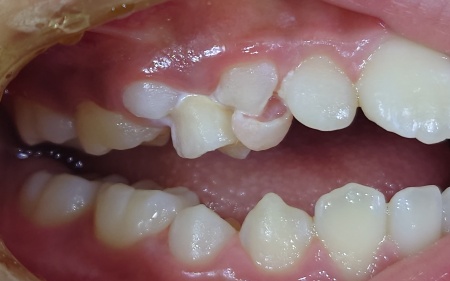

9歳女の子 永久歯が生えてきても自然に抜けず残っていた乳歯を抜いた症例

- 小児歯科

- 抜歯

- 治療期間の目安 -

- 治療回数の目安 1回

- 治療費総額の目安 保険診療内

治療のリスク

・持病をお持ちの方や、服用中のお薬の種類によっては、外科処置ができない場合があります ・外科処置後に腫れ、出血が生じる場合があります ・外科処置後に痛みが長引く場合があります。必要に応じ痛み止めを併用します...

by.エスペレ歯科・ホープデンタルクリニック